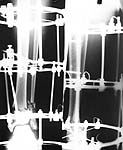

Why connecting rods are bent?

As Dr Finlayson commented the fragments are malaligned. The combination of wires and pins in the middle ring makes correction at least inconvenient though of course it is always possible to re-assembly the frame and include hinges.

It would be quite enough to have either a 6 mm half pin or a olive wire inserted in frontal plane just above the fracture. The pin or wire would help to move the distal part of the shaft laterally (and a bit back) to align the fracture.

See an example of the suitable assembly. The injury is not so severe as in your case but the fracture pattern dictates a quite similar mounting. Since in your case the distal fragment is even larger than in the example there is no need to use foot extension as dr M. Parihar said. A foot support looks enough.